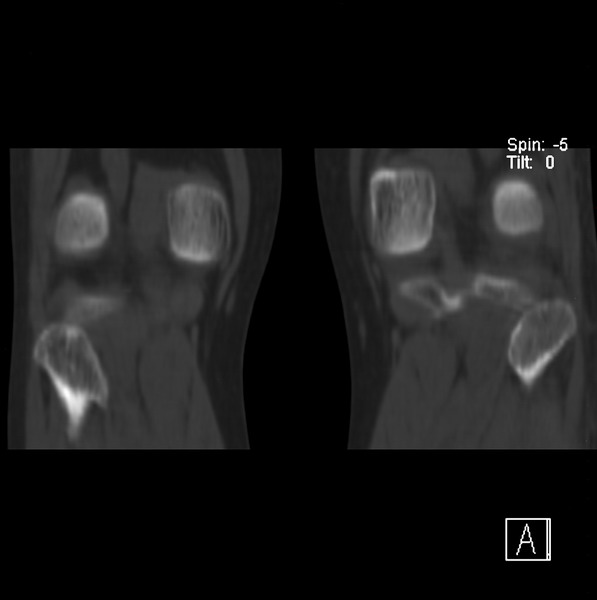

标题: CT21917:右腓骨小头是否骨软骨瘤? [打印本页]

标题: CT21917:右腓骨小头是否骨软骨瘤?

女、43.

不是骨软骨瘤,“牵拽征”,正常变异。有平片吗?

正常变异,“牵拽征”,比目鱼肌牵拽.

比目鱼肌附着点